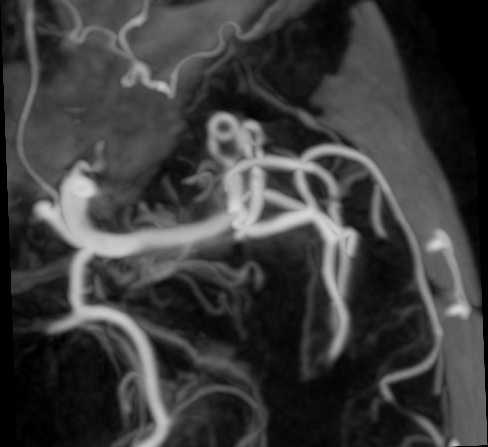

Angiografia cerebrale di controllo post-operatorio